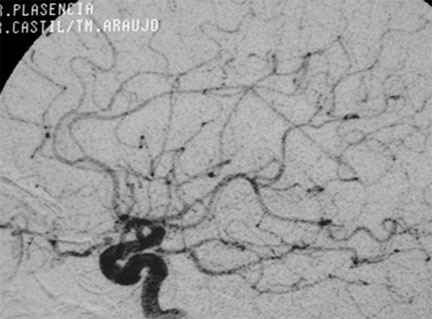

CASO 4 : Radiocirugía como tratamiento único en malformación arteriovenosa de mediano volumen en paciente joven con crisis convulsivas

IAngiografía al momento de la radiocirugía

Angiografía al año y medio después de la radiocirugía que muestra la curación de la paciente sin ningún efecto adverso ni secuelas.